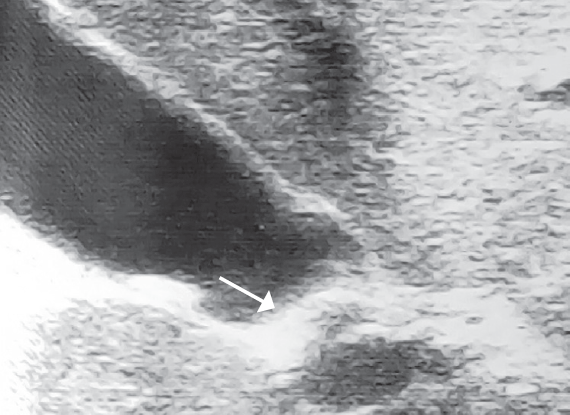

Research result. All patients with cholelithiasis identified different ways deformation in the area of gallbladder duct. One of the major causes of cholelithiasis in children are changes in the gallbladder duct. No patient has ever been found in concretions extrahepatic biliary passages. In patients with chronic stone-free cholecystitis pathology in the area of bladder flow was not found.